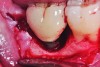

Fig 2. Clinical exposure of a circumferential lesion that demonstrates 3 mm of bone loss. No cement was present, suggesting that the lesion was of bacterial origin. Surface decontamination included citric acid.

Figure 2